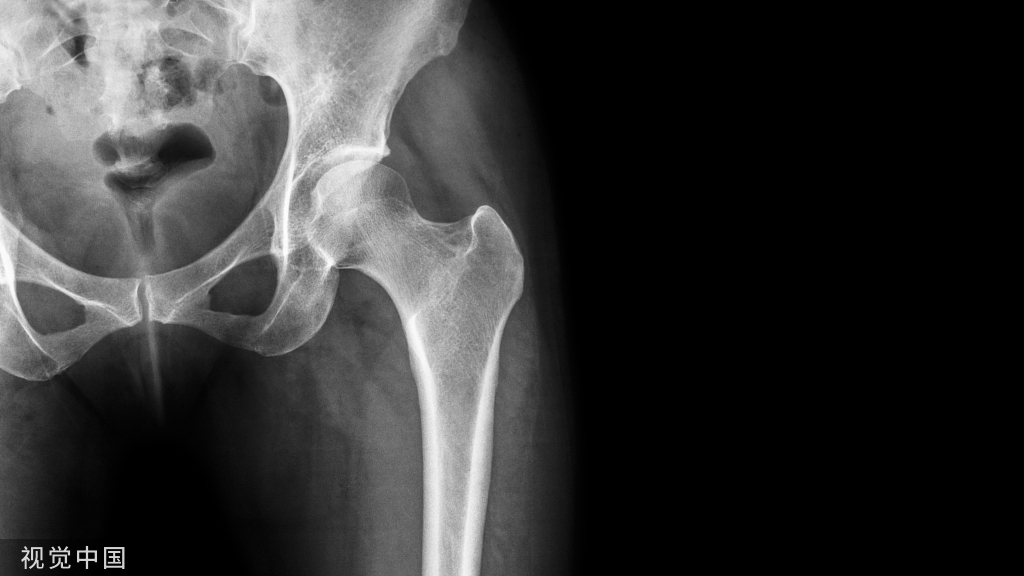

15椎弓根征

椎弓根征,又称眨眼猫头鹰征(Winking owl sign)

本征指的是在脊柱正位 X 线片上,一侧椎弓根投影消失,为「闭一只眼」(箭示),另一侧椎弓根投影存在,为「睁一只眼」(圈),相应棘突类似喙,总体形似一只眨眼的猫头鹰。

典型病例

病例 1. 女,37 岁,腰痛 4 月余,肺癌转移。腰椎正位片,示第 3 腰椎右侧椎弓环影破坏消失。

病例 2. 胸椎转移瘤。正位 X 线片示胸 11 左侧椎弓根投影消失(白箭),右侧椎弓根影存在(黑箭),形似眨眼的猫头鹰。

(引用自: https://radiopaedia.org/articles/ winking-owl-sign-spine)